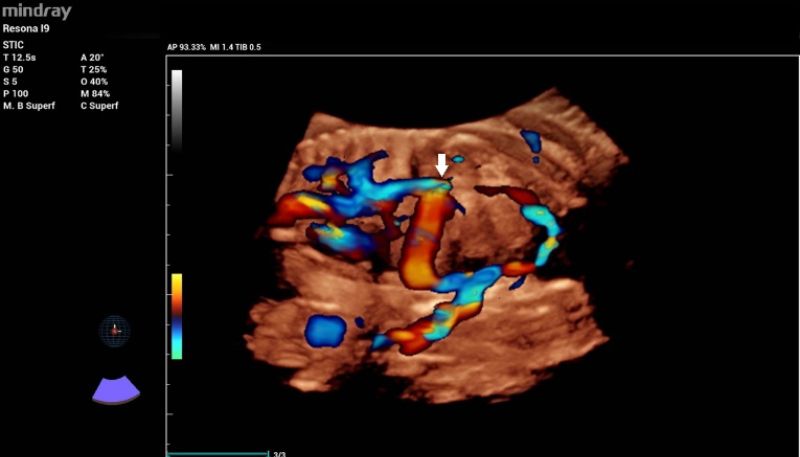

Additionally, a wide muscular ventricular septal defect (VSD) (Fig 2). and agenesis of the ductus venosus with extrahepatic drainage to the inferior vena cava (Fig 3). were diagnosed.

3D color reconstruction of the abnormal ductus venosus drainage into the inferior vena cava (white arrow)

Figure 3: 3D color reconstruction of the abnormal ductus venosus drainage into the inferior vena cava (white arrow).

6. In this particular case, 3D color Doppler reconstruction allowed detailed evaluation of the venous system and was crucial for understanding the ductus venosus abnormal drainage.